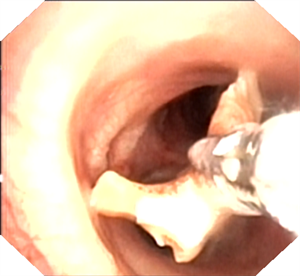

此时,消化内科吴主任直接接过 “接力棒”。在疼痛科主任朱华忠无痛麻醉监护及内镜护理人员配合下,成功取出异物——手表表带的生耳针。这一异物在支气管镜诊疗前,从患者支气管内咳出后又被吞入胃中。当异物被成功取出的那一刻,在场所有医务人员悬着的心终于放下。虽然当时已至凌晨一点多,但大家毫无疲惫之感,心中唯有成功救治患者后的喜悦。